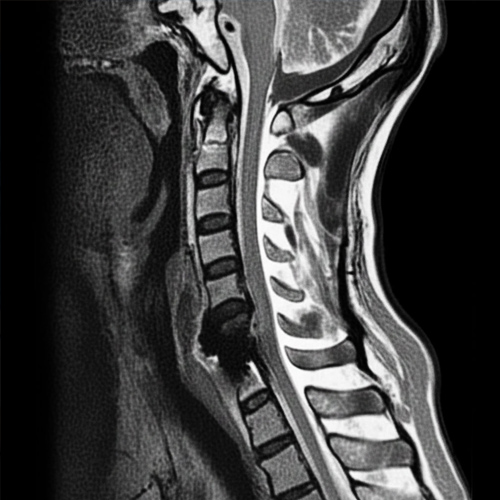

경추협착증

경추협착증은 경추(목 , 척추)의 척추관이 좁아져서 척추 신경이나 척수에 압박이 가해지는 상태를 말합니다.

경추(목뼈) 부의 척추관 협착증을 일컫는 말로 척추관이 좁아져 팔이나 다리로 가는 신경을 압박함으로써 증상이 나타나는 질환

협착증으로-신경이-눌린상태